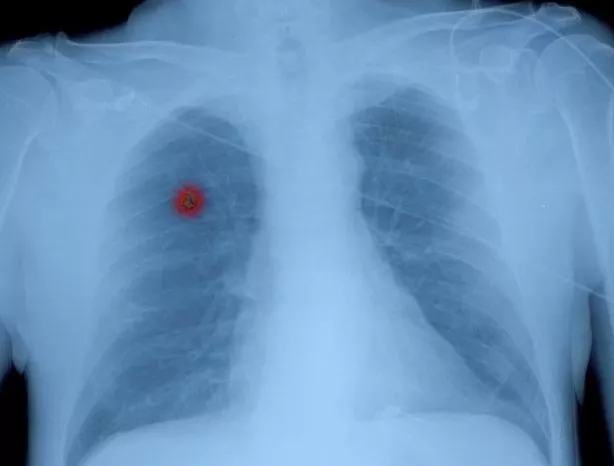

随着肺癌筛查项目的引入,越来越多的磨玻璃结节被CT扫描发现。磨玻璃结节肺癌的具体手术方式现在还有争议。磨玻璃成份占比常用来作为采取不同手术方式的依据。

磨玻璃结节所在的位置、大小、密度决定了手术切除方式的选择。无论哪一种手术方式,医生首先会做到病灶完整切除,然后在切“干净”的基础上尽量多保留正常肺组织,以便术后患者有更好的肺功能和生活质量。

3. 纯磨玻璃结节往往恶性程度低,可以考虑行切除较少的楔形或肺段切除;混合性磨玻璃结节,也就是混有实性成分的磨玻璃结节,一般情况下实性成分越多,恶性程度就越高,则一般行切除相对较多的肺段或肺叶叶切除术。